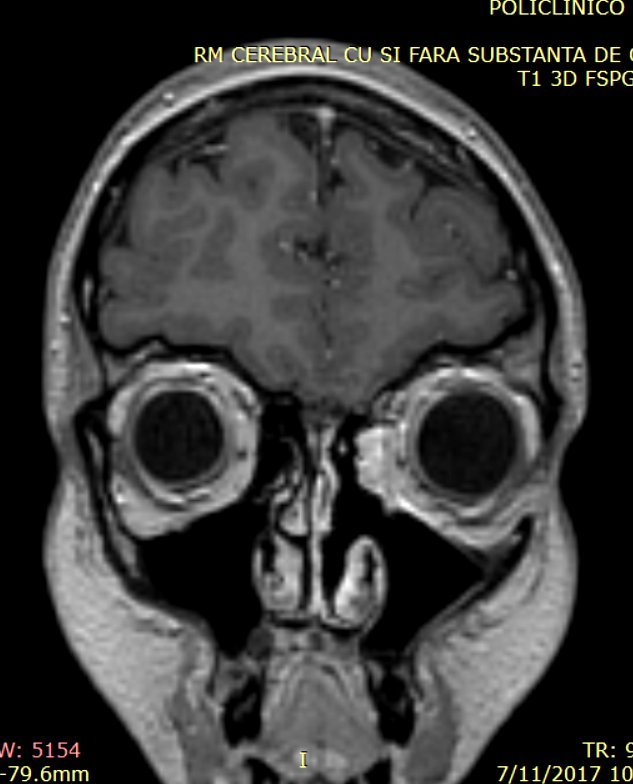

Pacienta efectuase încă din anul 2015 un examen RMN craniocerebral pentru explorarea lojei hipofizare în contextul SIADH, în care se putea vizualiza cu uşurinţă patologia tumorală rinosinusală, însă examenul ORL efectuat la acea dată a stabilit diagnosticul de polipoză nazală unilateral – fig. 1

Fig. 1: examen RMN craniocerebral cu substanță de contrast efectuat în anul 2015